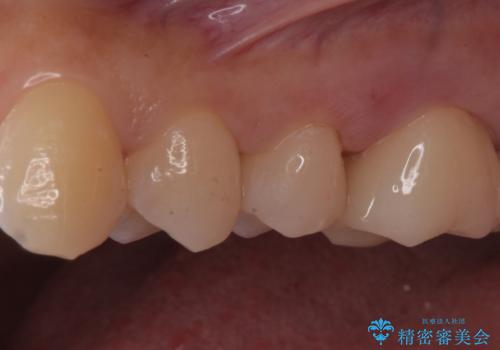

- 銀が目立つので白くしたいとの事で来院。

銀の詰め物を拡大鏡下で取り除き、う蝕がないことを確認してから

ZrCrの被せ物で治療を行いました。

また、一つ手前の歯に小さな虫歯があったため

e-maxインレーでの治療を行いました。

- ジルコニアクラウン・仮歯・e-maxインレー 19.8万円費用は治療当時の料金となります